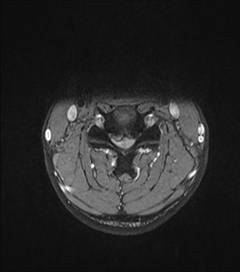

典型病例汇报1:中年男性41岁,因“行走不便2年,加重伴双手麻木2周”之主诉入院,症状主要为:颈部疼痛、僵硬,双下肢无力、行走不稳,双手麻木,协调性差,右手握笔困难。入院查体:步态不稳,C3-C7压痛、叩击痛,肢痛温觉减退,双上肢肢肌力5-级,双下肢肌力4-级,肌张力增高,双下肢腱反射亢进,病理征(+),行颈前路小切口突出椎间盘切除、前路颈椎桥形锁定植骨融合(ROI-C假体),无需前路钢板,术后四肢麻木明显缓解,右上肢精细动作明确增强,可写字,行走不稳消失,肌力基本正常,颈部活动度无明显受限。(1、图2)

图1 术前颈椎MRI提示颈椎退行性变,C4/5椎间盘突出、脊髓出现高信号改变,C4硬膜囊受压变形